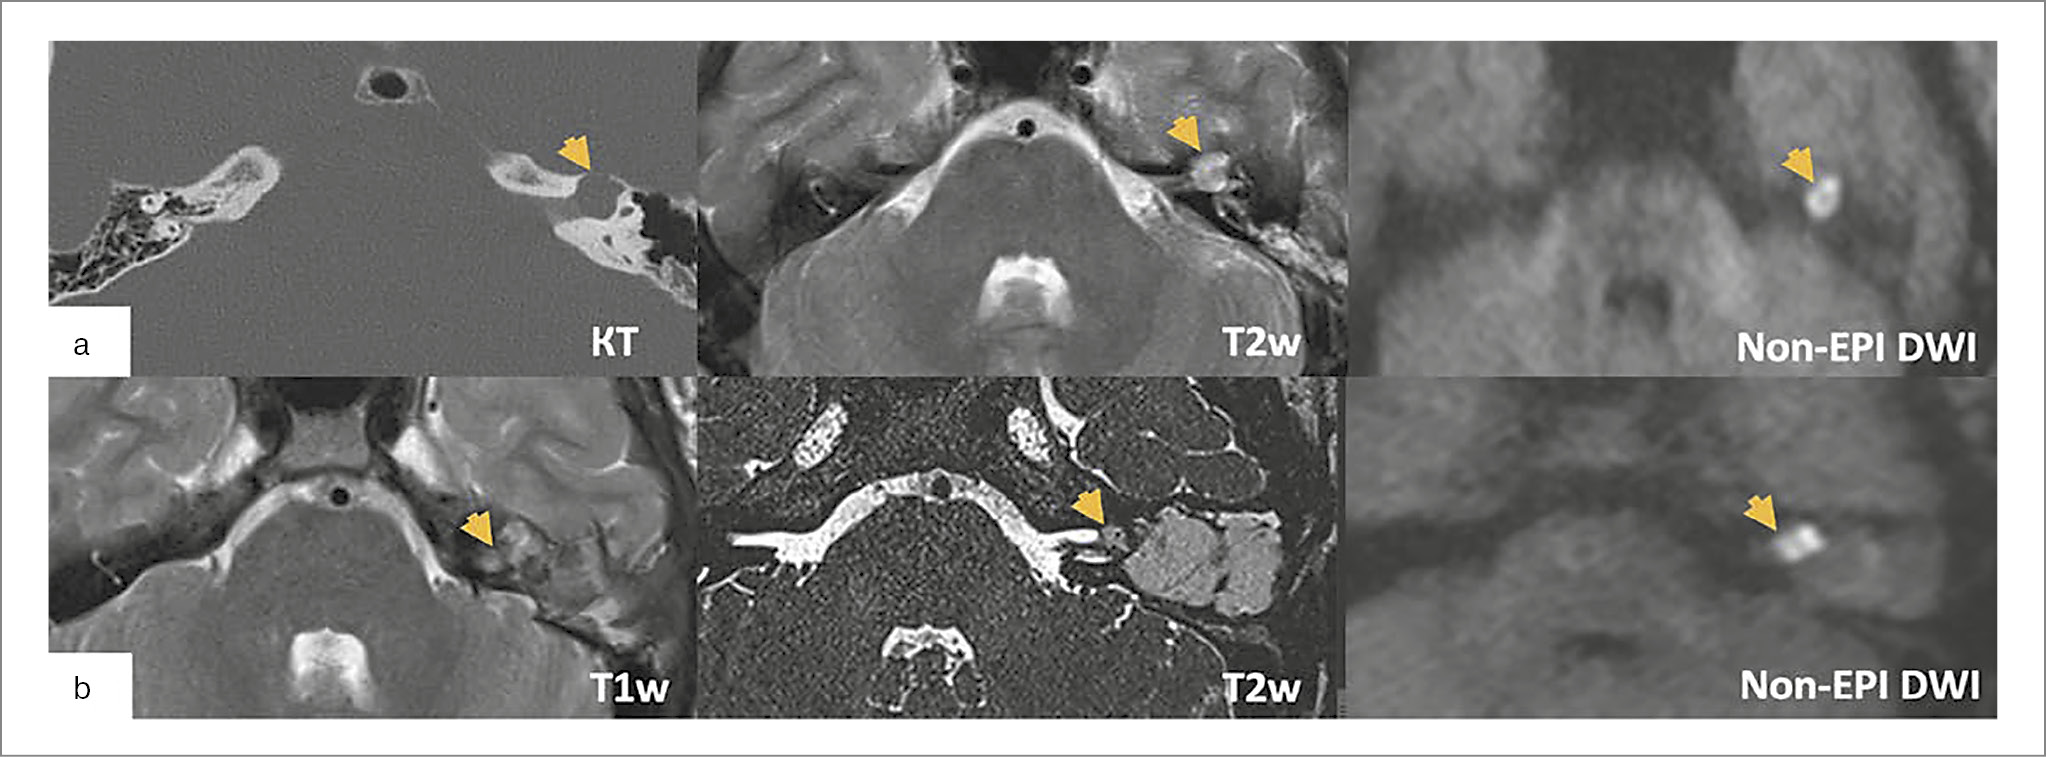

Ведущие методы исследования для установки диагноза – КТ височных костей и МРТ головного мозга. По КТ-исследованиям оценивается локализация процесса в структуре височной кости и латерального основания черепа, определяется хирургическая тактика. На данных КТ основаны наиболее актуальные современные классификации холестеатомы ПВК M. Sanna и D. Moffat и соав. [33, 36]. Холестеатома ПВК имеет тенденцию к агрессивному разрушению костных структур, может одновременно поражать несколько отделов височной кости и распространяться по супра-/инфралабиринтному ячеистому тракту к внутренней сонной артерии, верхушке пирамиды, клиновидной пазухе, в исключительно редких случаях – носоглотке; сзади к задней черепной ямке (ЗЧЯ) и сигмовидному синусу; медиально может доходить до основания ВСП и ската; вниз до яремного отверстия, канала подъязычного нерва, мыщелка затылочной кости [37]. Изолированное развитие холестеатомы в ВСП встречается редко, а разрушение стенок ВСП не указывается в классификациях, между тем несет в себе ключевое понимание о типе необходимого доступа, достаточного для санации и определения методики закрытия послеоперационной полости. Для более детальной оценки вовлеченных в патологический процесс анатомических структур, в том числе ВСП, разработана оценочная шкала CLIF (APO) [38].

Исследования МРТ производятся в стандартных режимах (Т1 – гипоинтенсивный сигнал, Т2 – гиперинтенсивный), они дополняют КТ в ходе дифференциальной диагностики. Большое значение имеет non-EPI (В1000) DWI – последовательность, высокоспецифичная для холестеатомы, играет большую роль в определении рецидивов, особенно при закрытых техниках (облитерация послеоперационной полости и закрытие наружного слухового прохода cul-de-sac); рис. 2. В случае протяженного контакта холестеатомы с магистральными сосудами и возможной необходимости перекрытия просвета сигмовидного синуса необходимо проведение МРТ с внутривенным контрастированием либо в режимах MPА (ToF, PC, 4D), чтобы оценить достаточность венозного оттока по контрлатеральной стороне [21].

Рис. 2. Исследования пациентов с холестеатомой ПВК, разрушающей ВСП: а – врожденная супралабиринтная холестеатома, локализующаяся в области дна ВСП; b – рецидив врожденной холестеатомы ПВК в области ВСП.

Одни из первых симптомов, характерных для холестеатомы ПВК с разрушением ВСП, – снижение слуха и функции мимической мускулатуры на стороне поражения. Холестеатома сдавливает прилежащие ЧМН, вызывая локальную демиелинизацию. При распространении процесса во внутреннее ухо часто развивается глухота.